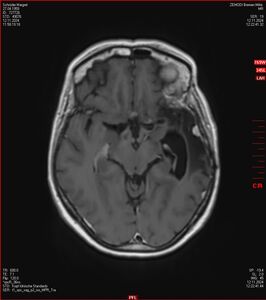

MRT vom 12. November 2024

So nun ein paar neue Bilder aus meinem Kopf. (Durch klicken bekommt man eine größe Ansicht eines Einzelbildes).

Die letzten drei Bilder Zeigen aus meiner Sicht den Tumor, der im Jahr 2021 bestrahlt wurde.